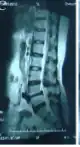

-

MRI of the lumbar spine, intervertebral disc degeneration -